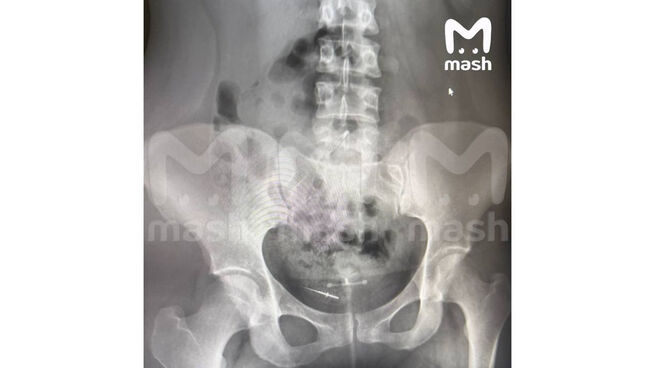

По данным Telegram-канала Mash, 26-летняя женщина посетила стоматологический кабинет. После визита у нее возникли сильные боли в области живота. Рентген показал, что игла переместилась в нижнюю часть тела. Сообщается, что пациентке потребуется хирургическое вмешательство.